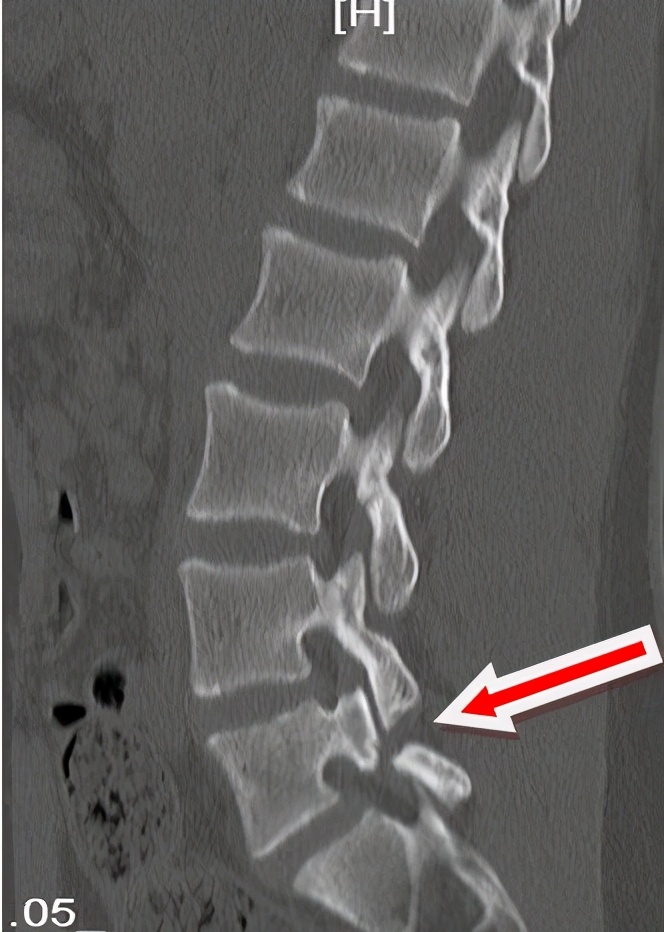

对于腰椎峡部裂的诊断,主要是依据临床症状、体征、X 片及CT 检查。X 主要包括站立、负重侧位、前后位及左右45°斜位,腰椎双斜位X 线片是峡部裂首选影像学检查,可清晰显示峡部的纵行或斜形裂隙,主要表现为上关节突之间的部份出现透亮带,即所谓的 “狗带项圈征”。